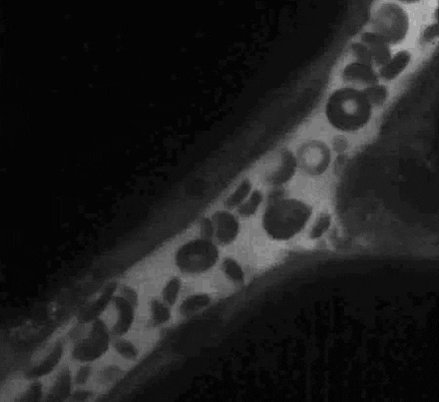

٣- يُعتبر الإلتهاب طريقة حماية للجسم وتعد كريات الدم البيضاء الخلايا الأساسية في جهاز المناعة لأنها تصنع الحموضة اللازمة لإذابة المايكروبات والعوامل الممرضة والسم للقضاء عليها وإطلاق بعض الانزيمات الي تذيب المايكروبات.

وما نننسى الخلايا البلعمية : تلتهم المايكروبات ( فيروسات - باكتيريا - خمائر - فطريات - الخلايا الميتة والمخلفات ) تشبه بمصرف النفايات الي ما نحتاجها بالجسم . وتتحفز بالأحماض وممكن اذا كلنا فيتامين سي ( مصدر طبيعي) يتحفز لأنه يحفزه ونفس الشي لخل التفاح الي يزيد حموضة الجسم .

اذا تضررت خلايا الدم البيضاء وتعرضت للأختراق تضحي وقتل نفسها في سبيل الدفاع عن الجسم كامل لأنها لو سمحت للمايكروب بالدخول راح تكون آلة ناسخة ومساعده له في انتشاره.